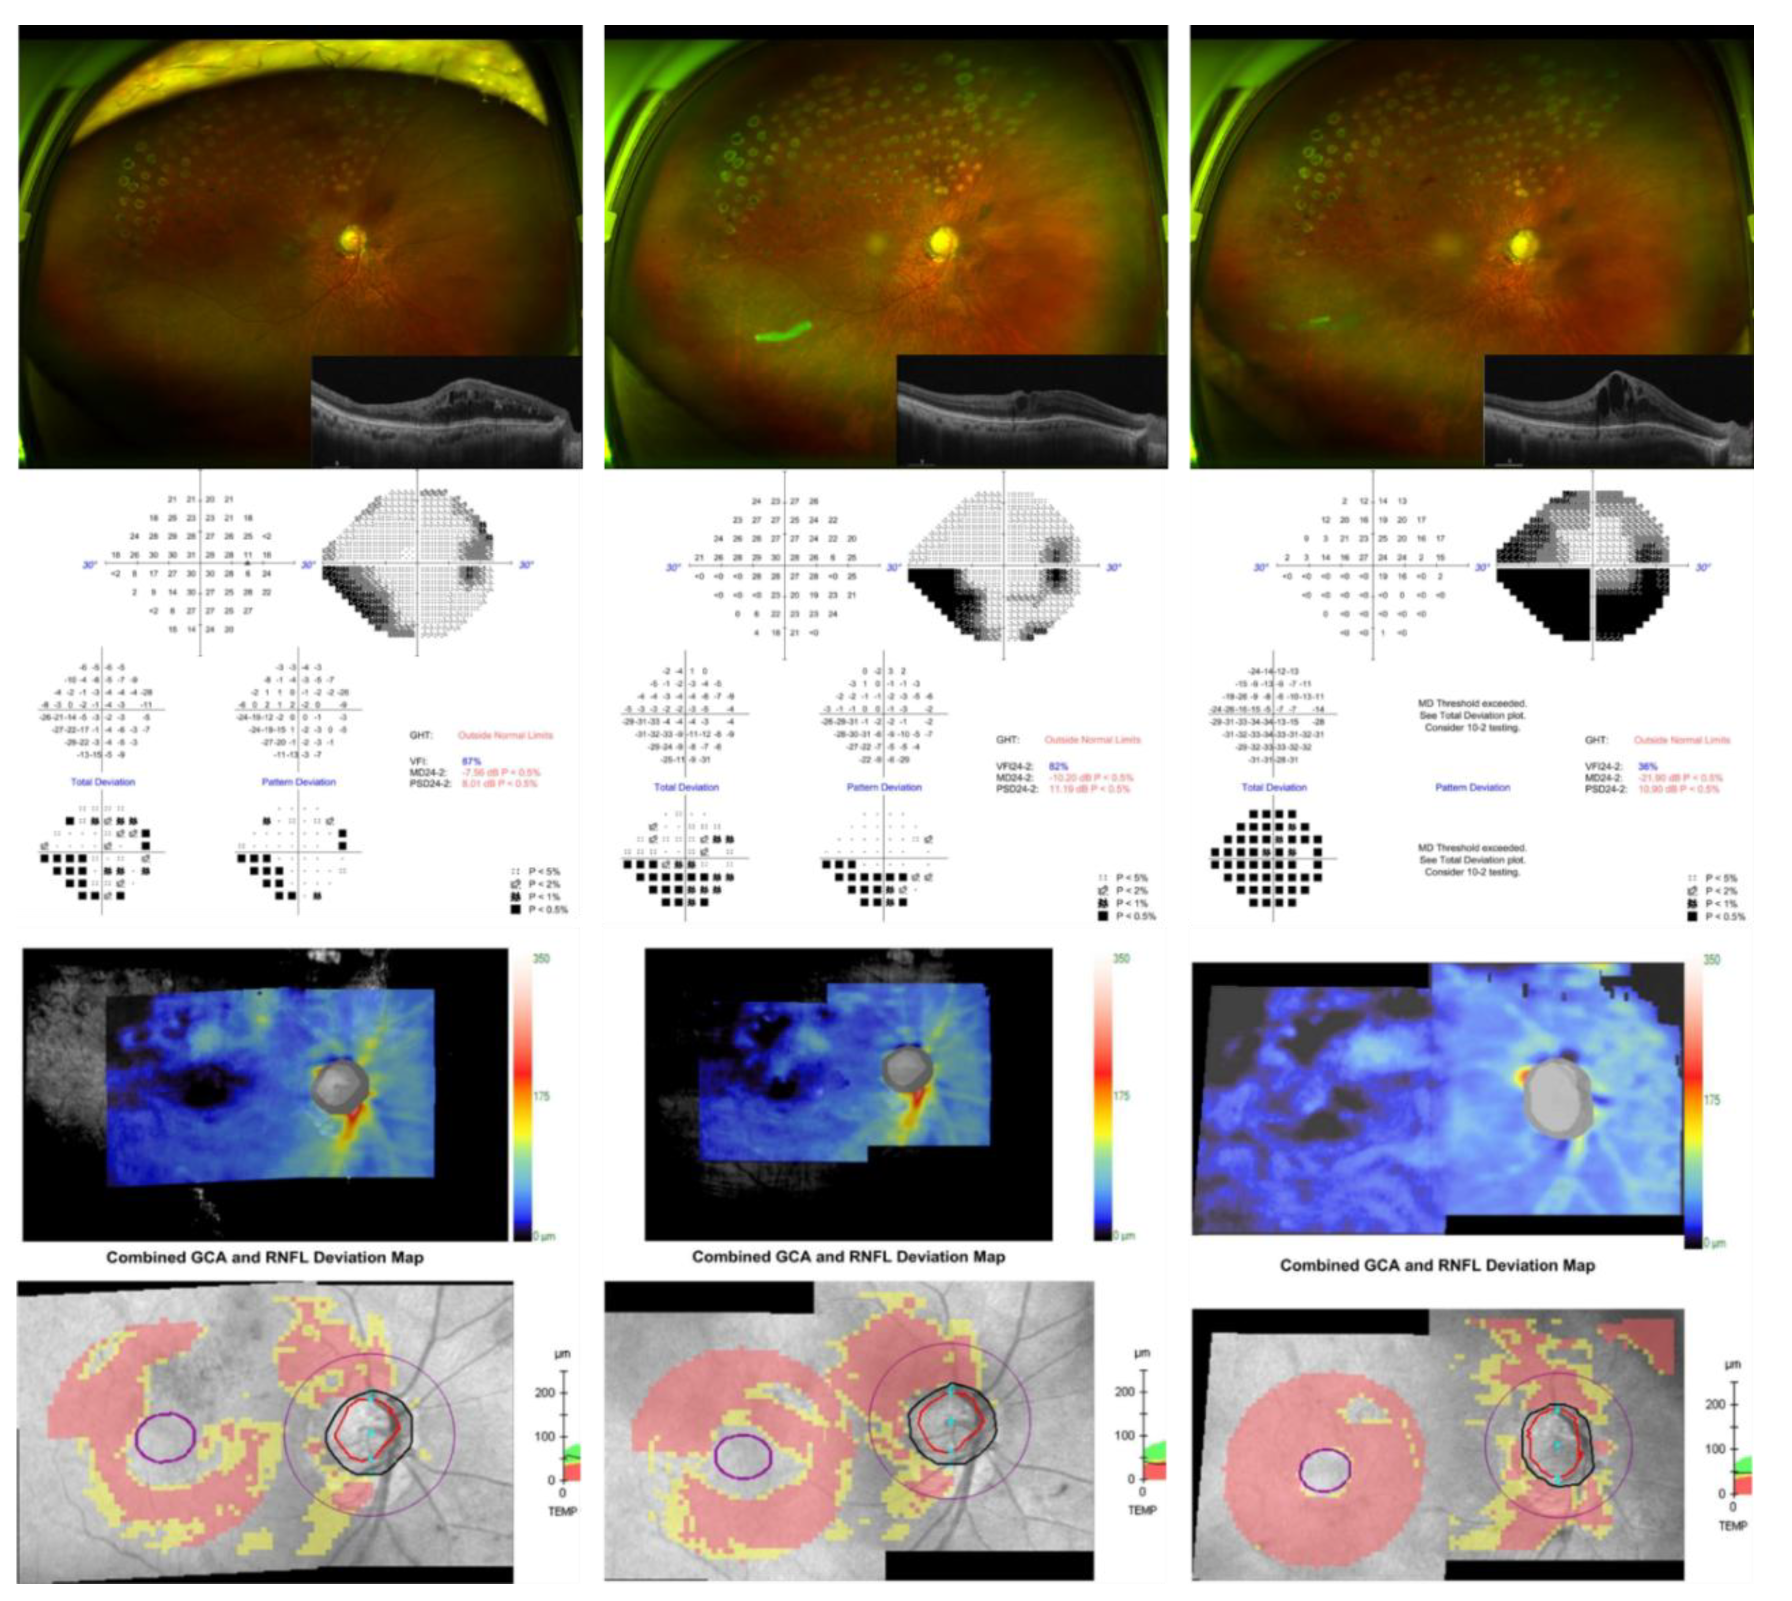

The postoperative course was uneventful. IOP decreased to 13 mmHg on postoperative day 7 while using DTFC and remained stable at 15 mmHg on the last follow-up at 12 months. There were neither intraoperative nor postoperative complications. Notably, the patient underwent two additional intravitreal Ozurdex injections for recurrent BRVO-related macular edema, which remained well controlled, as confirmed by serial macular OCT images showing resolution of cystoid changes and restoration of foveal contour. (Figure 5)

Figure 5. Longitudinal changes in optical coherence tomography (OCT) showing resolution and stabilization of macular edema. (left) Preoperative OCT showing severe cystoid macular edema with a central subfield thickness of 472 μm. (center) At three months postoperatively, the macular contour improved significantly with a central subfield thickness of 251 μm. (right) At twelve months, the foveal profile remained stable (262 μm) with no recurrence of intraretinal fluid, consistent with anatomical recovery and sustained macular edema control.